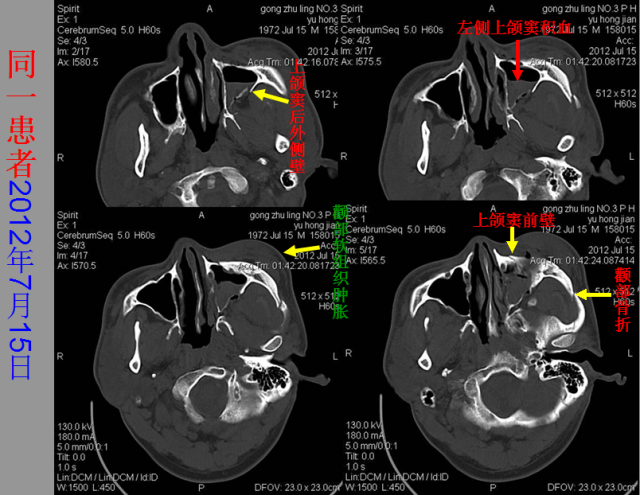

急性颅脑损伤篇

急胸症篇